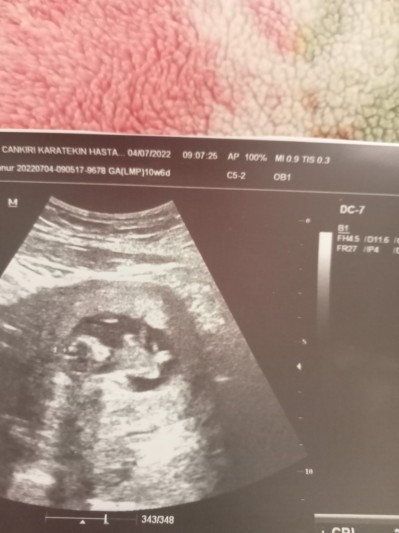

Sizce nedir bayanlar

Gebelik haftası 14+2